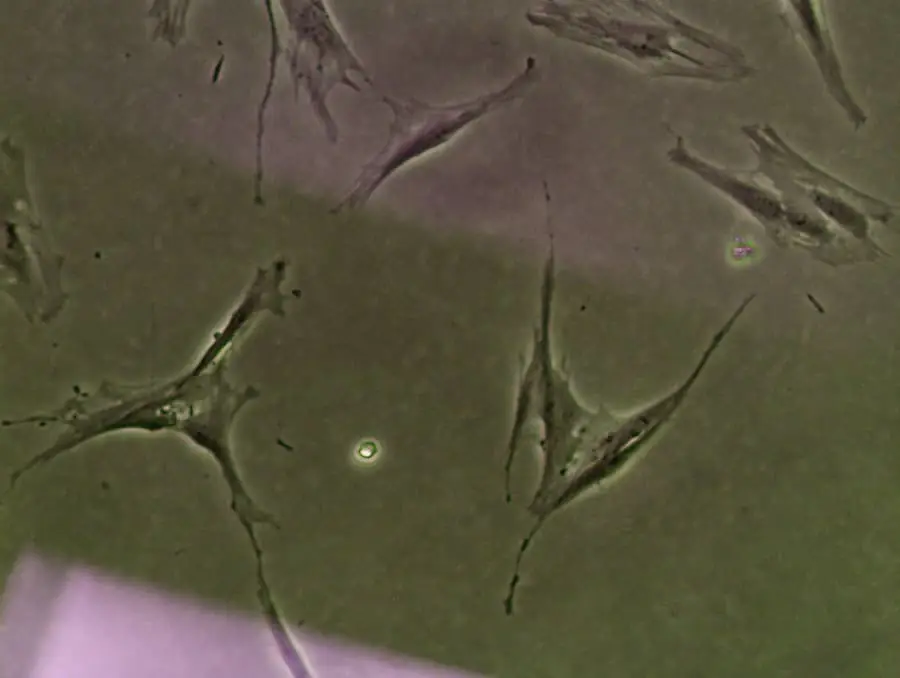

使用顯微鏡監測干細胞的活力